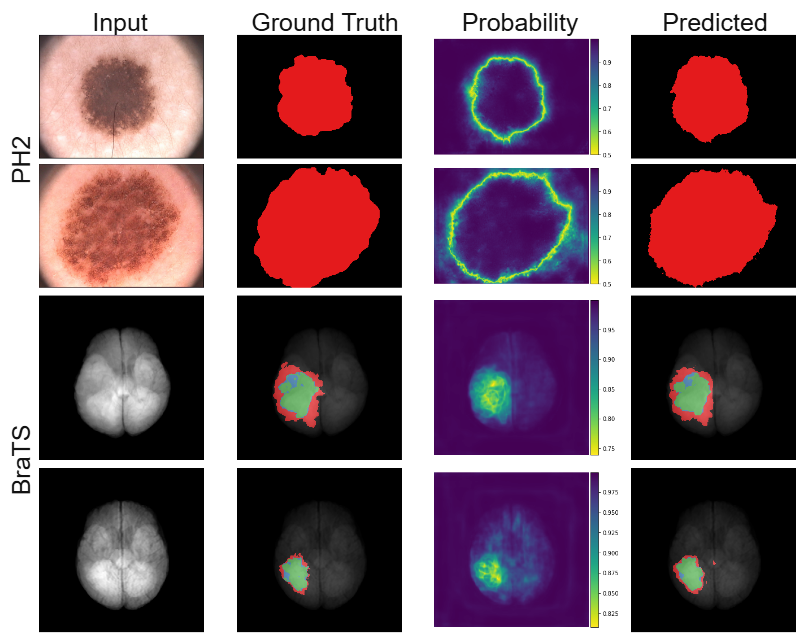

Refer to caption

Figure 4: Illustration of ground truth and predicted segmentation, along with the predicted probability for the true class for two examples from each dataset. The red in the PH2 example represent the binary mask. The red, blue and green in the BraTS dataset represent enhancing tumor, tumor core and whole tumor respectively.